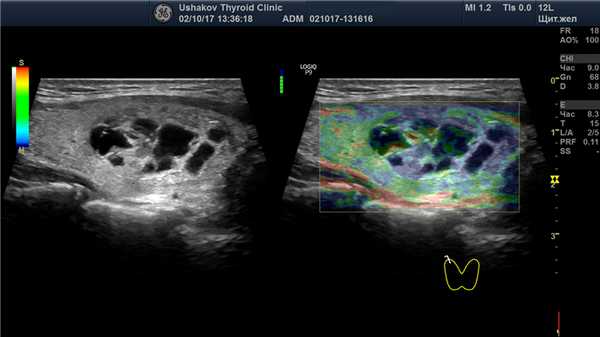

В правой доле щитовидной железы в центрально-каудальной части почти до её краев (в поперечной проекции) расположен овоидоподобной формы узел 22,9х20,7х33,1 мм (7,4 мл), окруженный по всему периметру чёткой гипоэхогенной границей-контуром, значительно неоднородный за счет множественных анэхогенных (жидкостных) участков (около 70% от объёма узла), преимущественно с чёткими границами в виде узких перегородок с изо- и гиперэхогенной (фиброзной) тканью и изоэхогенной тканью по периметру узла; при ЭДК заметно примыкание к узлу с кранио- и каудальной сторон магистральных сосудов, и умеренный кровоток по части периметра и мало интенсивный внутри узла (в перегородках); при эластографии SR 2,8 (3,3 - в обл. некоторых перегородок). Вне узла ткань изоэхогенная, почти однородная; в краниальном полюсе 21,2х15х15,1 мм (2,3 мл), а также медиально. В режиме ЦДК и ЭДК кровообращение в этой ткани в малой степени усилено.

Рис. 27.6. Пример 1. (правая доля, продольная проекция; ЭДК).

К узлу с краниальной и медиальной сторон подходят магистральные сосуды, создавая вокруг него, почти по всему периметру, умеренной интенсивности кровоток, с малой насыщенностью в тканевых перегородках узла.

Все признаки узла (в режимах В, ЭДК, ЦДК) в этом примере указывают на доброкачественный процесс. Форма узла приближена к правильной, стремится повторить форму доли. Узел имеет чёткую границу и гипоэхогенный (сосудистый) контур по всему периметру, распределение сосудов и. закономерные изменения внутри. Доброкачественность остаточной ткани подтверждается и при эластографии (SR 2,8).

Следует проследить источники сосудистой сети узла (в данном случае, она исходит из нескольких магистральных сосудов из ветвей верхней и нижней щитовидных артерий). Такая особенность важна, поскольку сообщает о закономерном поступлении к узлу нервных стимулов по нервным волокнам, сопровождающим сосуды.

Кровеносная сеть в узле также закономерна. Она соответствует биологически естественному распределению сосудов разных порядковых уровней в ткани узла, по мере формирования его сегментов. В данном случае мы наблюдаем явный окружной кровоток (рис. 27.6) и в межсегментарных участках (по краю внутриузловых сегментов ткань сохраняется дольше именно за счёт более полноценного обеспечения кровью (и меньшего напряжения)).